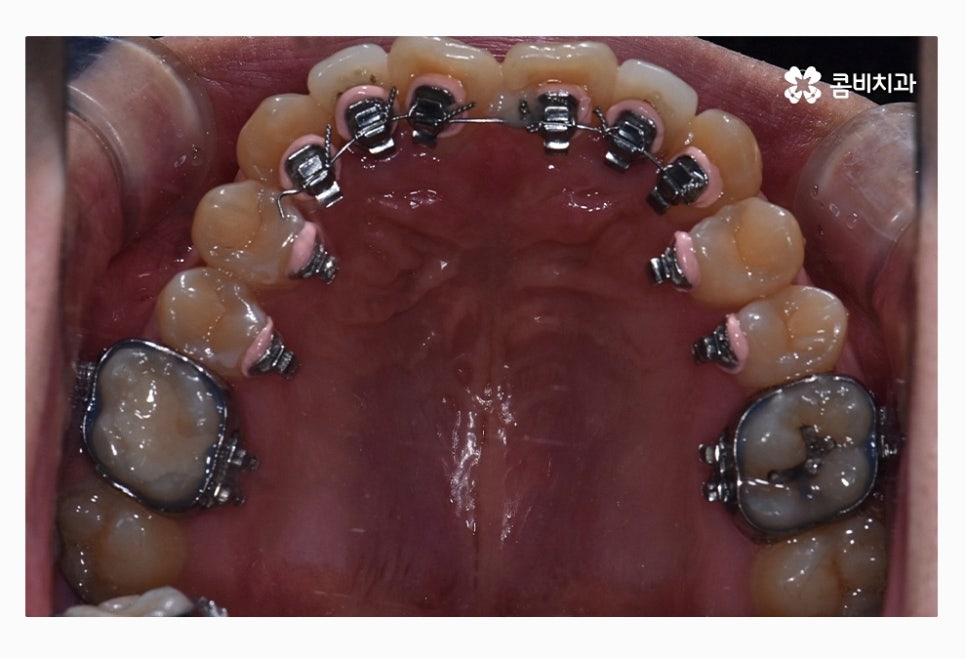

콤비교정이 시작된 후 사진이며 윗니는 교정 장치가 눈에 띄지

않는다는 점이 콤비교정의 특징이라고 할 수 있는데요.

위 사진을 다시 한번 자세히 보면 윗니는 치아의 안쪽에

교정 장치가 부착이 되어 있는 모습이며

아랫니는 일반적인 교정 방법으로 장치가 부착되어 있어요.

위 사진은 교정 장치를 부착한 초기 사진이며

아래는 콤비교정 진행하고 약 1년 정도 지난 후 사진이라고 할 수 있는데요.

윗니에서 앞니가 유독 삐뚤어져 있던 상황이었는데

반듯하게 자리를 잡아가고 있으며 아랫니에서도

삐뚠 부분이 있었는데 가지런하게 자리를 잡아가고 있어요.